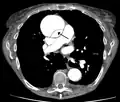

Computed tomography angiography is a fast, non-invasive test that gives an accurate three-dimensional view of the aorta. These images are produced by taking rapid, thin-cut slices of the chest and abdomen, and combining them in the computer to create cross-sectional slices. To delineate the aorta to the accuracy necessary to make the proper diagnosis, an iodinated contrast material is injected into a peripheral vein. Contrast is injected and the scan performed using a bolus tracking method. This type of scan is timed to injection to capture the contrast as it enters the aorta. The scan then follows the contrast as it flows through the vessel. It has a sensitivity of 96 to 100% and a specificity of 96 to 100%. Disadvantages include the need for iodinated contrast material and the inability to diagnose the site of the intimal tear.

CT with contrast demonstrating aneurysmal dilation and a dissection of the ascending aorta (type A Stanford)